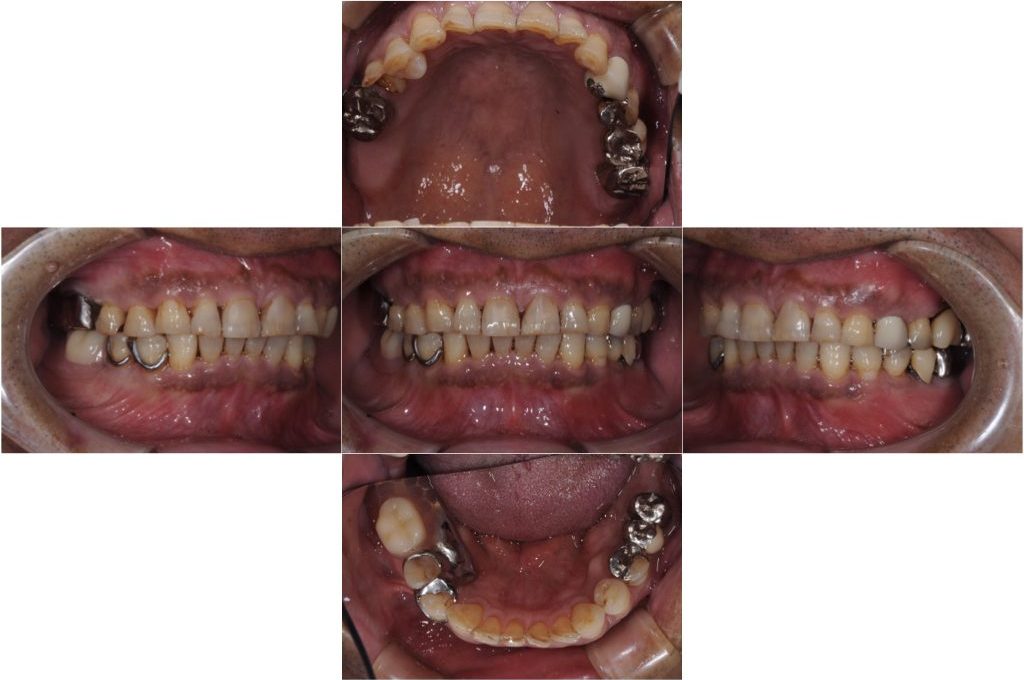

年齢 62歳

性別 男性

初診日 2019年11月

主訴 被せ物が外れた

治療経過 主訴は被せ物の脱離であったが、診査の結果、現状抜歯を余儀なくされる歯も見受けられた。

患者様は現在使用している義歯にも満足しておらず固定式でしっかり噛めるようになりたいとの希望もあったためインプラント治療を提案した。

天然歯は全体的にかなりすり減りが認められるため、セラミックの材質についても周りの歯の形態に馴染むものを選択した。